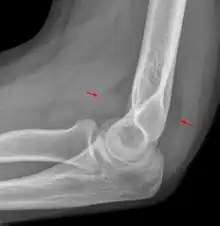

The fat pad sign, also known as the sail sign, is a potential finding on elbow radiography which suggests a fracture of one or more bones at the elbow. It may indicate an occult fracture that is not directly visible. Its name derives from the fact that it has the shape of a spinnaker (sail).[1] It is caused by displacement of the fat pad around the elbow joint. Both anterior and posterior fat pad signs exist, and both can be found on the same X-ray.

In children, a posterior fat pad sign suggests a condylar fracture of the humerus. In adults it suggests a radial head fracture.

The fat pad sign is invaluable in assessing for the presence of an intra-articular fracture of the elbow. An anterior fat pad is often normal. However a posterior fat pad seen on a lateral x-ray of the elbow is always abnormal. The patient will be unable to flex their elbow and requires orthopaedic input.[2]